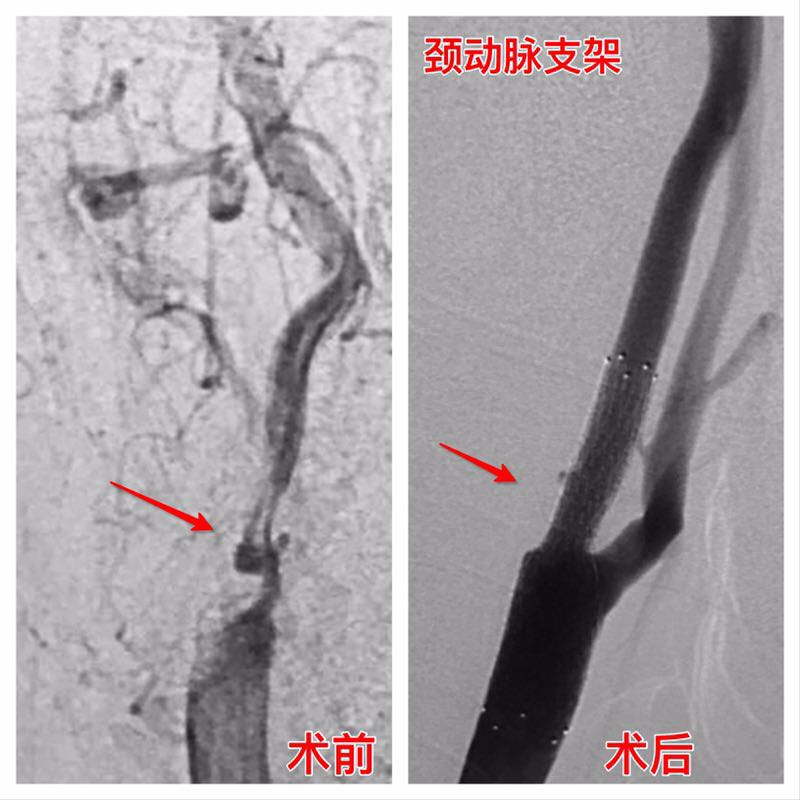

我院成功开展首例颈动脉狭窄支架植入手术

患者邹某,男性,73岁,因反复头昏伴晕厥十年余,来我院查拟“头晕原因待查”收住入院。尽管一直予以活血化瘀、稳定斑块等对症处理,患者在住院期间又多次出现一过性晕厥现象,病情加重刻不容缓,经过我院DSA检查明确诊断为:1、右侧颈内动脉起始部重度狭窄;2、右侧椎动脉V4段闭塞;3、脑梗塞;4、高血压病。高博士及我院神经介入团队分析病情,考虑患者右侧椎动脉V4段闭塞已丧失开通机会,反复头昏伴晕厥与同侧颈内动脉狭窄有直接关系,只有尽快解决狭窄满足右侧大脑半球血供才能改善上述症状。经过术前各项准备后于6月24日在局麻下行“右侧颈内动脉起始部支架植入术”,术中先于右侧颈内动脉岩骨段置入保护伞装置并释放,再于狭窄处用Cordis Aviator 5-30mm球囊在10个大气压下预扩张,复查造影显示扩张满意后最后再用eV3 Protégé 9-40mm支架成功置入狭窄处,手术过程非常顺利,术后头晕不适症状明显改善,3天后痊愈出院。